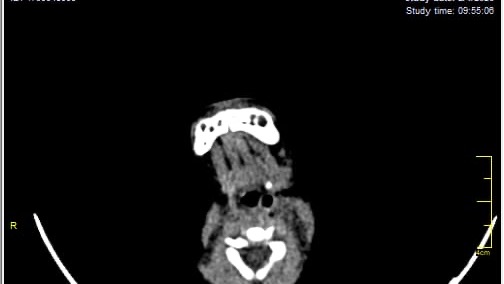

A 3-month-old baby in my family is facing a life-threatening brain condition. Medical reports and imaging confirm serious neurological injury that requires immediate, specialized treatment outside Gaza—care that is not available here.